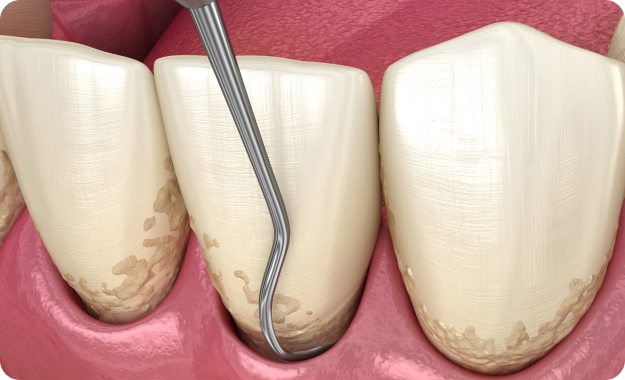

- 스케일링

- 치아의 표면과 잇몸 안에 붙어있는 치석과 치태를 치과용 기구를 이용해 제거하는 시술입니다.